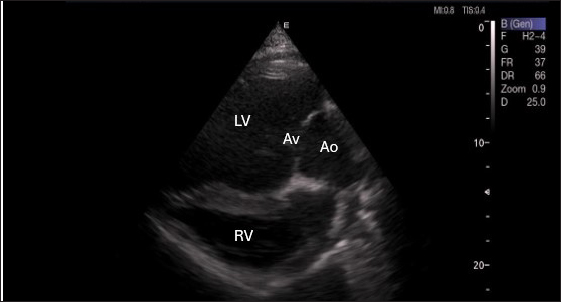

Left parasternal ultrasonography

Figure 5 shows an image of the ventricles, atria, and interventricular septum in the caudal long-axis four-chamber view acquired by positioning the probe perpendicularly in the fourth intercostal space or longitudinally in the fifth intercostal space with a little clockwise rotation. Every camel had a perfectly normal heart anatomy, including ventricles, tricuspid valve, mitral valve, and atria on both sides. During the fourth ICS image of the LVOT, the probe was turned slightly further cranially and twisted somewhat counterclockwise (Fig. 6). No camel is complete without an oblique aortic cross-section.

Fig. 6. Left parasternal long axis of 18 racing camel showing LOVT=left ventricular outflow tract. LV=left ventricle, Av=aortic valve, Ao=aortic artery, Rv=right ventricle.